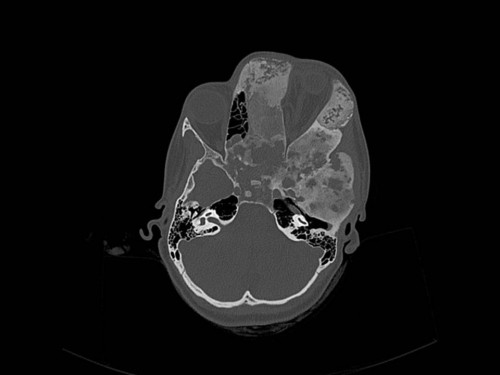

Knochendeformitäten seit der Geburt

Fall-ID: 712

ICD: M85.09

Autor*in: Sandra Klipp

Eine 16-jährige Patientin kommt in eine MKG-chirurgische Praxis zur Abklärung der weiteren Vorgehensweise bzgl. ihrer Erkrankung.

Sie betrachten die angefertigten Röntgenbilder. Welche der folgenden Röntgenbefunde ist korrekt? Ossäre Auftreibungen im Bereich …

- A… der Mandibula links.

- B… des Os frontale links.

- C… des Os zygomaticum links.

- D… des Os temporale links.

- EAlle genannten Aussagen sind korrekt.

Bildgebung - OPAN 2004